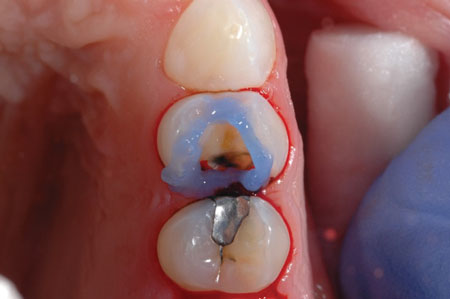

After preparing the tooth, a viscous phosphoric acid gel was carefully traced around the margins of the preparation for a selective enamel etching technique and allowed to react for 15 seconds (figure 2). This was followed by copious water rinsing. Isolation was achieved using the Palodent Plus Sectional Matrix System (Dentsply Sirona), and Prime&Bond Elect was scrubbed over the entire preparation of tooth No. 12 followed by a gentle stream of oil-free air for five seconds to thin the material and evaporate the acetone solvent (figure 3).